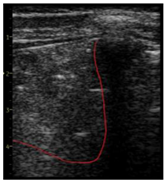

| LUS Score | 0 Points | 1 Point | 2 Points | 3 Points |

| Image | ![]() | ![]() | ![]() | ![]() |

| Description of image | Normal or physiological pattern displaying A-lines (right part), along with two sparse B-lines (yellow arrows) per intercostal space | Three sparse B-lines (yellow arrows) per intercostal space, accompanied by pleural abnormalities, such as irregularities or thickening (orange circle) | Small peripheral consolidations smaller than 1 cm (red dotted area), a small area with ‘white-lung’ appearance, adjacent coalescent or merging B-lines | Substantial peripheral consolidations (marked with red) wider than 1 cm with the presence of air bronchograms (hyperechoic areas inside); the image is from an infant with bacterial pneumonia not included in this study |